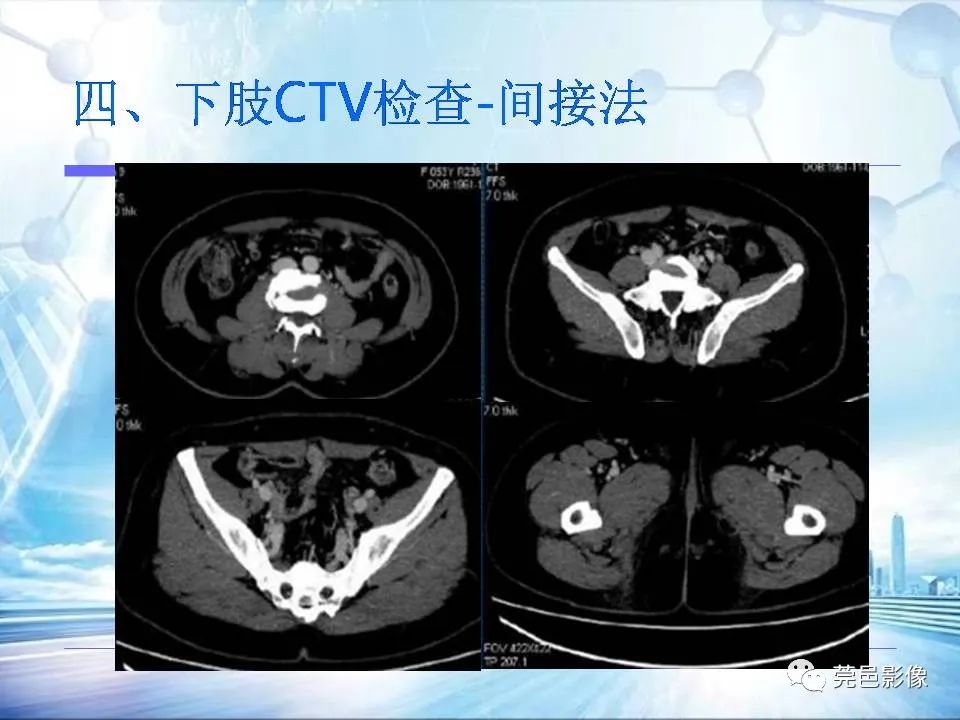

浅谈下肢静脉CTV的应用体会